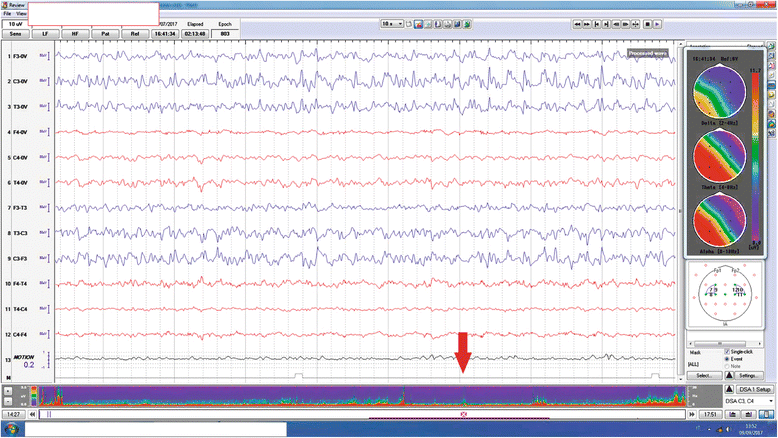

Figures